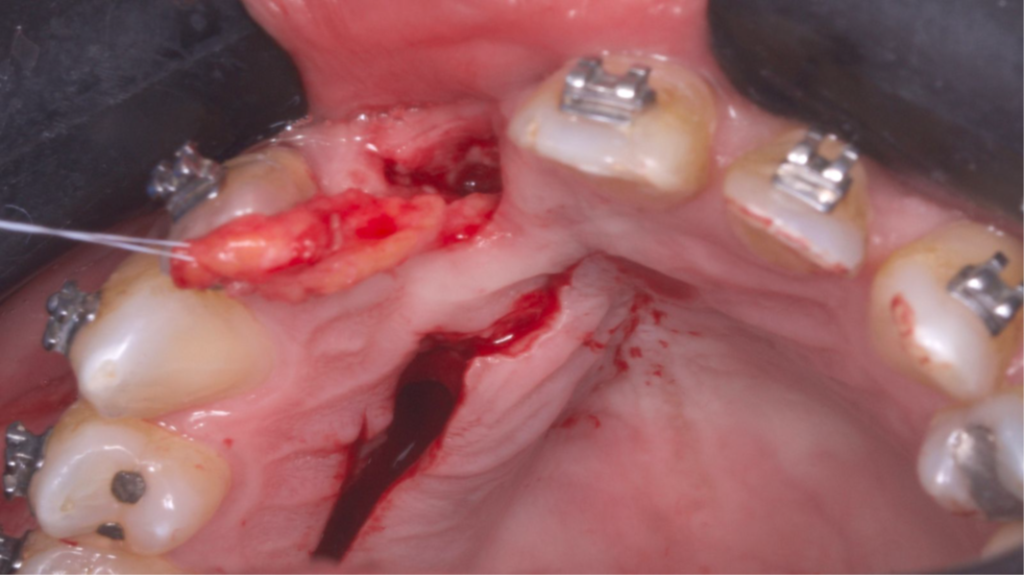

O tecido ósseo que suporta a estética rosa sofre diferentes modificações após uma extração e o biótipo gengival do paciente desempenha um papel importante na resolução multidisciplinar da instalação de um implante na zona estética. Uma alternativa viável de técnica para obter resultados estéticos e funcionais é a técnica VIP-CT (Vascularized Interpositional Periosteal Connective Tissue Flap).

O retalho VIP–CT, inicialmente idealizado para a proteção de enxertos em área anterior de maxila, pode também ser usado para aumento de rebordo na região anterior, apresentando benefícios em comparação com outras técnicas de enxertos de tecidos conjuntivos por obter um enxerto próximo ao leito receptor e completamente viável (por se manter com pedículo), bem como pode evitar a exposição de uma regeneração óssea guiada (ROG) ou enxertos ósseos de grande morbidade, como com a técnica de Khoury ou enxertos onlay.

Paciente do sexo masculino encaminhado pela Ortodontia para a instalação de um implante ao nível do dente 1.1 (Figura 1), com diastemas mésio-distais de 2mm, para utilização do implante como ancoragem absoluta e melhor andamento da movimentação ortodôntica.